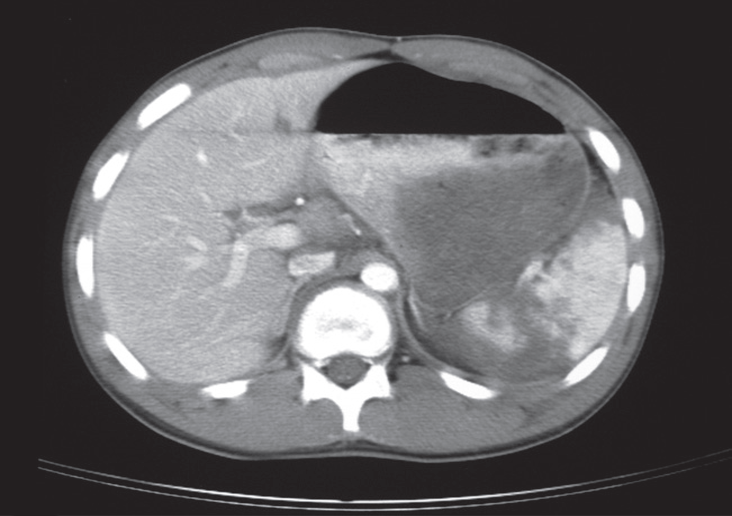

Splenic injury may be detected by ultrasound, but CT is a superior method of investigation it demonstrates the damage to the spleen and intraperitoneal blood and visualize injuries to other abdominal organs.

Rupture

on CT. The spleen is shattered with low density blood adjacent to the fragments.